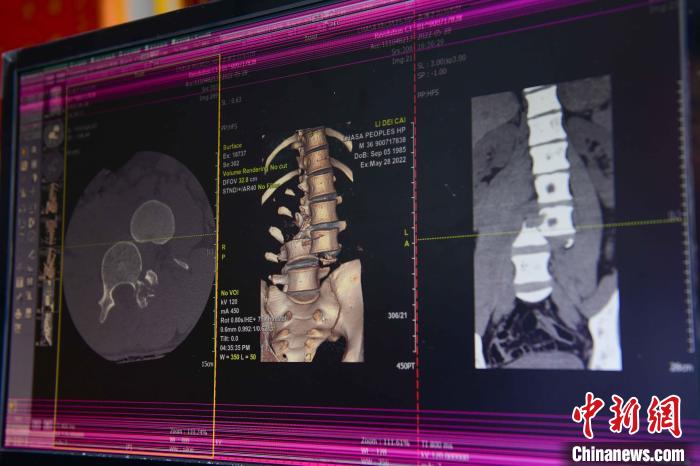

圖為患者術(shù)前,腰3/4脊柱骨折伴脫位?!≡髑?攝

通道開(kāi)通后,拉薩市人民醫(yī)院完成了兩例脊柱創(chuàng)傷截癱患者的救治。一例23歲的病患為胸12椎體爆裂骨折伴截癱,另一例36歲的病患腰椎體骨折脫位伴雙下肢癱。按照脊髓損傷救治綠色通道流程,術(shù)前充分快速完善相關(guān)檢查,充分術(shù)前評(píng)估,向患者詳細(xì)交代手術(shù)風(fēng)險(xiǎn),入院當(dāng)天急診行手術(shù)治療。